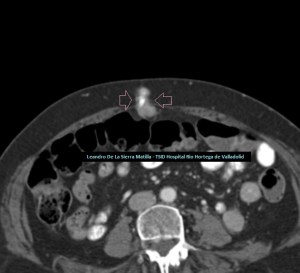

Cambiamos a una sonda lineal para un estudio más detallado, observando una LOE hipoecogénica con zonas híper-isoecogénicas, heterogénea, sólida, sin contenido de asas intestinales ni de grasa, con bordes mal definidos y con flujo doppler en su interior, ubicada dentro de la cavidad umbilical (FIGURAS 5, 6 Y 7)

5

6

7

Se realiza Tc con contraste para completar estudio de extensión, en el que se confirman los hallazgos visualizados en la ecografía incluido el nódulo metastásico umbilical (FIGURA 8).

8